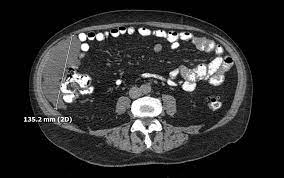

Intra Abdominal Benign Multicystic Peritoneal Mesothelioma Sciencedirect

Intra Abdominal Benign Multicystic Peritoneal Mesothelioma Sciencedirect from ars.els-cdn.com